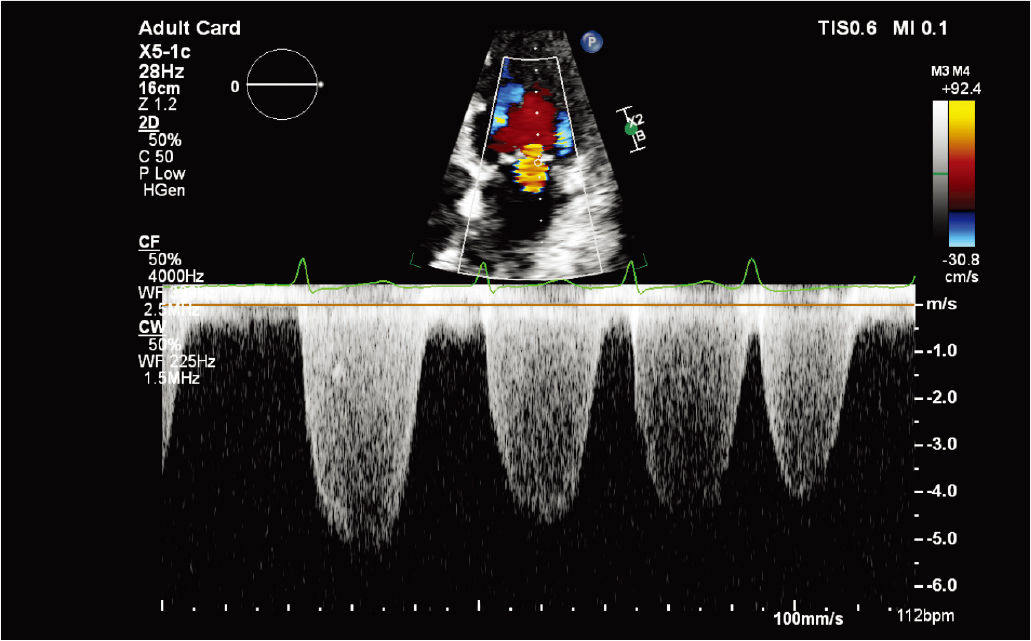

X5-1c 探头彩色多普勒二尖瓣返流(MR) |

X5-1c 磁共振 CW 多普勒探头 |